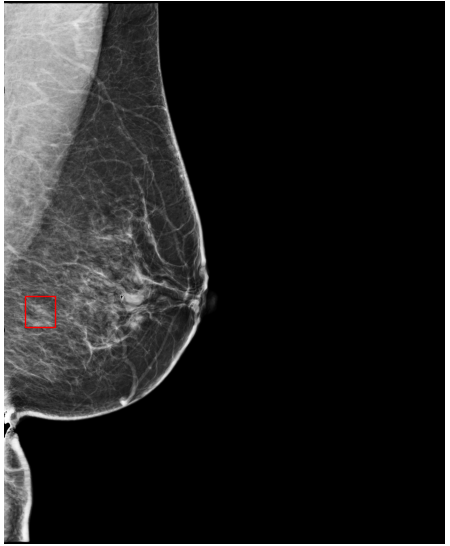

The EMBED and CSAW-CC datasets originally consist of images in DICOM format, which are converted into 16-bit grayscale PNG images for consistency and compatibility. Following the pre-processing procedure outlined in (Yala et al.,, 2021), we enhanced image quality and removed background artifacts—such as textual annotations commonly present in mammography images—by applying a contour detection procedure. All contours in the image are detected, and only the largest contour, corresponding to the breast tissue, is retained. This contour is then used to create a mask that isolates the breast region from the background. The isolated breast image is resized to a size of 1664×20481664\times 2048 pixels while preserving the aspect ratio. Finally, the resized image is normalized and converted to a 16-bit format.

5.3 Comparison of Deformation Field Quality

Table 5: Quantitative comparison of deformation field quality. NJD: percentage of negative Jacobian determinants. Std. dev. Jacobian: standard deviation of the Jacobian determinant.

Dataset Method NJD (%) \downarrow Std. dev. Jacobian \downarrow EMBED FeatAlign 2.7096 (2.6808-1.7383) 0.4599 (0.4562-0.4640) FeatAlignReg 0.0385 (0.0171-0.0791) 0.0889 (0.0855-0.0931) ImgAlign / ImgFeatAlign 0.0013 (0.0012-0.0015) 0.1408 (0.1403-0.1413) CSAW-CC FeatAlign 3.6970 (3.6667-3.7270) 0.5965 (0.5897-0.6030) FeatAlignReg 0.0059 (0.0049-0.0071) 0.1329 (0.1323-0.1334) ImgAlign / ImgFeatAlign 0.0008 (0.0006-0.0009) 0.1402 (0.1397-0.1406)

Table 5 reports the quality of deformation fields across methods, measured by the Percentage of Negative Jacobian Determinants (NJD) and the standard deviation of the Jacobian determinant. Image-based registration methods, ImgAlign and ImgFeatAlign, achieve the highest deformation quality, exhibiting the lowest NJD values and minimal standard deviation across both datasets. These results show that image-based approaches produce smooth, spatially coherent, and anatomically plausible deformation fields.

In contrast, FeatAlign (feature-based registration without regularization) shows poor deformation quality, with elevated NJD values and high variability, suggesting implausible and unstable transformations. Introducing regularization in FeatAlignReg significantly improves performance, reducing both NJD and standard deviation. However, it still falls slightly short of the quality achieved by image-based methods.

Overall, these findings underscore the superiority of image-based registration in generating anatomically consistent deformation fields and highlight the critical role of regularization in improving the plausibility of feature-based alignment approaches.

Refer to caption

(a) FeatAlign

(b) FeatAlignReg

(c) ImgFeatAlign/ImgAlign

(d) FeatAlign

(e) FeatAlignReg